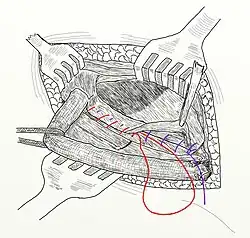

Ryc. 8. Pierwszy tzw. „szew Bassiniego” 1. Aponeurosis musculi obliq. ext.; 2. Musculus obliquus internus; 3. Musculus transversalis; 4. Fascia transversalis; 5. Peritoneum; 6. Ligamentum inguinale.

Ryc. 9. Warstwy szwów zakładanych w trakcie operacji m. Bassini: zielona nitka – tzw. szew Bassiniego zakładany na okostną; czerwona nitka – szew powięzi poprzecznej; niebieska nitka – szew mięśniówki z więzadłem pachwinowym.